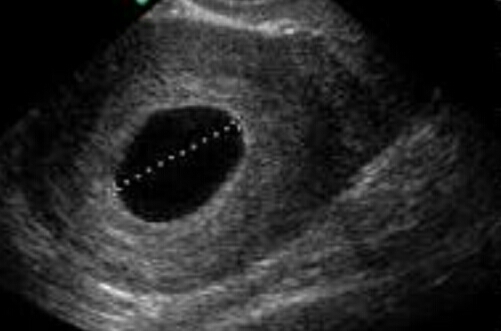

Была вчера на приёме у врача, сделали УЗИ, показало плодное яйцо без эмбриона.

Врач посоветовала подождать 10дней, может ошиблись с датой зачатия, и эмбрион появится